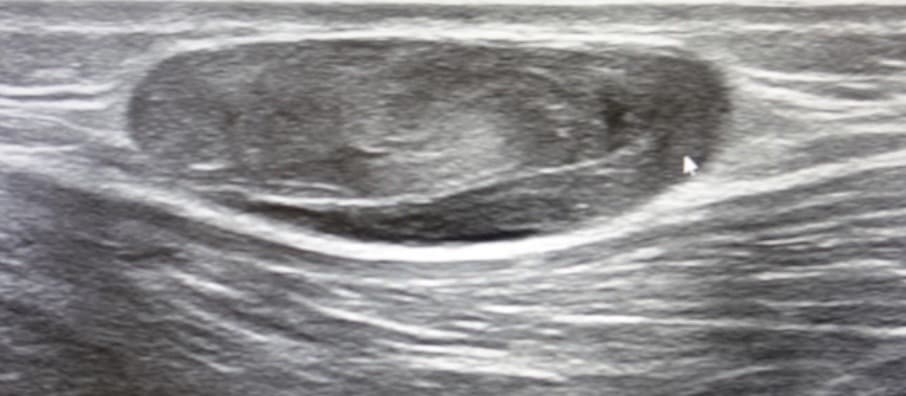

혈관 내피세포기형(endothelial malformation)은 혈관종(hemangioma)과 혈관기형으로 나눌 수 있다. 다시 림프관형, 모세혈관형, 정맥형, 동-정맥형, 혼합형 등으로 세분하기도 한다. 초음파 검사에서 혈관종은 낮은, 같은, 높은 에코 등 다양한 혼합형의 불균질 한 종괴로 보이고, 흔히 주변의 연조직과 경계가 불분명한 침윤성(infiltrative) 병변으로 보인다. 조직사이의 경계, 지방, 주변 연조직과의 경계는 낮은 에코로 보이는 것이 보통이며, 그 안에는 색도플러에서 에코가 없거나 낮은 에코의 혈관 분지를 보인다. 정맥돌(phlebolith)이 작은 석회화와 소리그림자를 동반하여 보이는데, 이는 기질화혈 전(organized thrombus) 안의 비정상조직 석회화(dystrophic calcification)이다.

혈관종 초음파 영상 혈관분지를 가지는 종괴 병변이 보이면 혈관종일 가능성이 높고, 종괴보다는 혈관 덩어리(tangle of vessels)가 보이면 혈관 기형일 가능성이 상대적으로 높다. 혈관종이나 동-정맥기형은 다른 혈관 기형보다 혈관이 굵고 그 수가 더 많다. 혈관종이 의심될때, 악성종양의 과혈관성 및 비정상조직 석회화를 감별해야 한다. 단순 촬영에서 특징적인 정맥돌을 확인하는 것이 도움이 되기도 한다. 경피적 조직생검이 필요할 수도 있다.